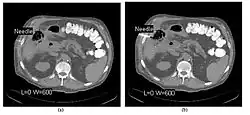

CT Fluoroscopy

- CT Fluoroscopy (CTF) has also been referred to as Continuous CT or Real-Time CT since it involves generating tomographic images at sufficiently high frame rates to allow guidance of needle placement in small or deep-seated lesions. Applications can include biopsy of thoracic lesions, biopsy/drainage of pelvic lesions, vertebroplasty and drainage/aspiration of intracranial haematomas. The advantages of CTF include increased target accuracy and reduced procedure times[45].

- The major difference to a conventional CT system is that high speed reconstruction techniques are applied, and that an operator panel, exposure footswitch and image monitor are installed in the scanning room for use by the interventionist. Controls are generally available for table movement, gantry tilt, laser grid definition and fluoroscopic factors. The other significant operational change relates to the choice of tube current which is typically 30-50 mA in CTF. This should be compared with typical screening currents used in conventional fluoroscopy of up to 5 mA, so that CTF can be regarded as a high dose procedure. In this context, additional beam filtration can be introduced automatically for CTF procedures to reduce patient exposure by up to 50%, for example. Furthermore, the use of protective gloves and needle holders can reduce the radiation exposure to the hands of the interventionist.

- The value of N is typically 30o, 45o or 60o, with frame rates of 12, 8 and 6 frames per second, respectively. In the case of 60o updates and 6 frames per second, the delay between each image is 0.17 seconds. A Last-Image-Hold (LIH) technique can be used while the image is being updated with the resulting time lag being considered by the interventionist in terms of biopsy technique. Example images are shown in Figure 7.15.11. The display of three adjacent slices of thickness 5 mm with MDCT scanning can be used to improve visual feedback to the interventionist as the needle progresses. In addition, multi-planar reconstructions (MPR) and volume rendered 3D images can be used to enhance fine control.